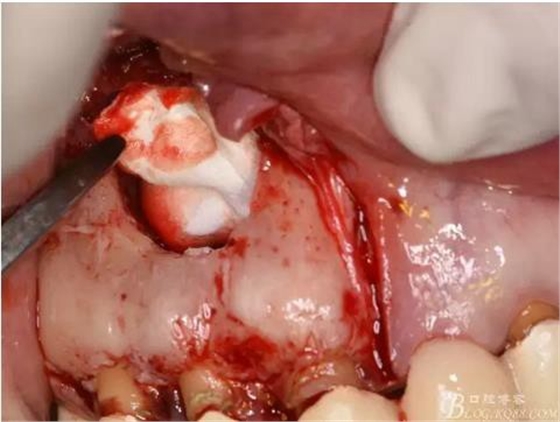

圖10.剝離囊壁